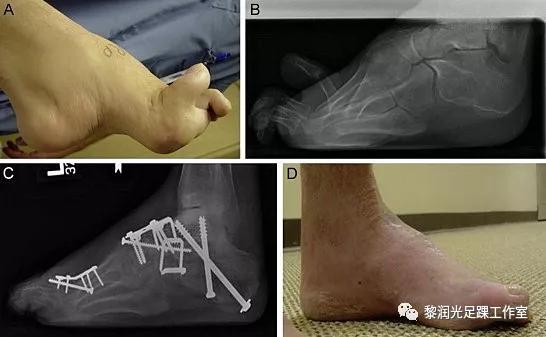

3.3骨性稳定性手术(截骨或关节融合)

如果患者足踝畸形较重,单纯行软组织平衡手术仍不能矫正或恢复稳定性,那么需要行足踝骨性手术,行截骨或关节融合术。

(CMT病人高弓内翻足,行软组织松解肌腱转位以外,需要行多处截骨术,术后足的外观以及功能得到改善)